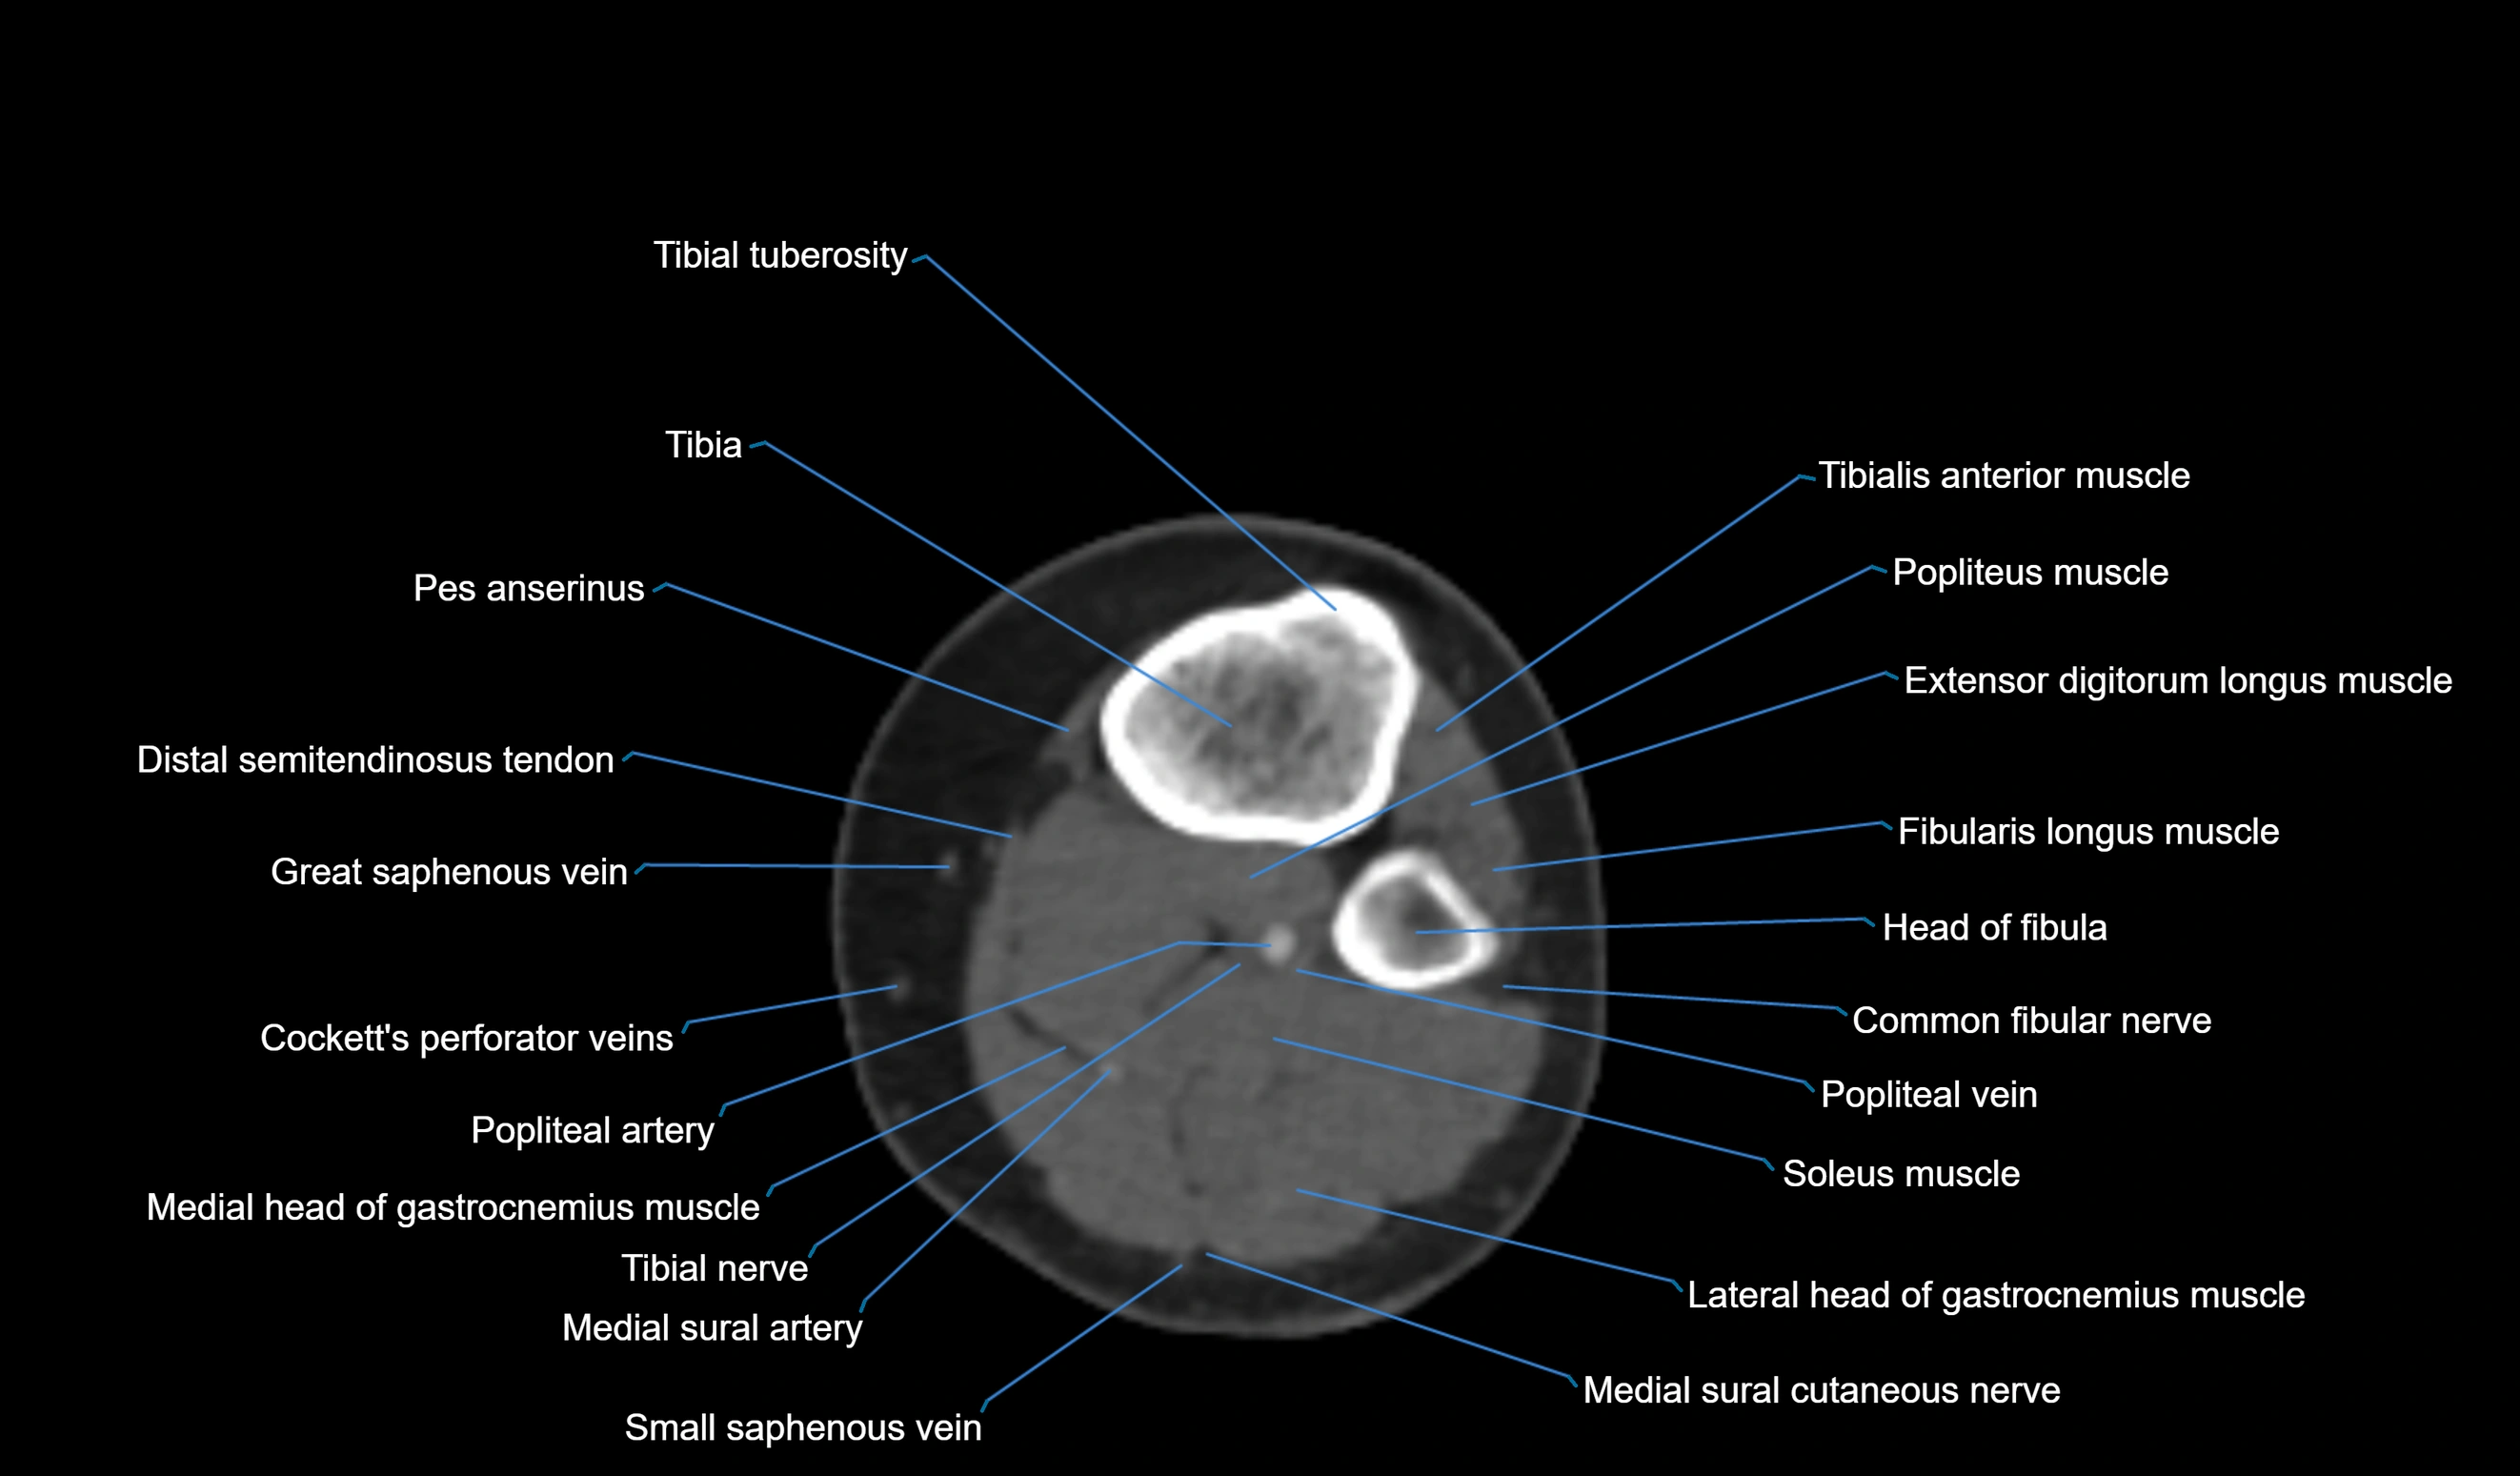

- Extensor digitorum longus muscle

- Fibularis longus muscle (peroneus longus muscle)

- Head of fibula

- Lateral head of gastrocnemius muscle

- Medial head of gastrocnemius muscle

- Popliteal artery

- Popliteal vein

- Soleus muscle

- Tibia

- Tibial nerve

- Tibial tuberosity

- Tibialis anterior muscle